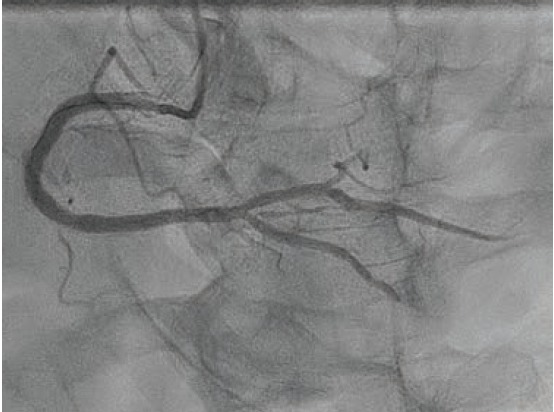

Further predilation was performed with a 3.0 mm x 21 mm NC Takeru™ PTCA balloon dilation catheter, after which the 6 French IVUS catheter was finally able to traverse the diseased segment.

Based on the distal reference diameter of 3.6 mm (Figure 3), we tried to perform one more round of pre-dilation with a 3.5 mm Emerge™ Monorail PTCA dilatation catheter (Boston Scientific). This did not cross, and resulted in kinking of the LiquID® guide catheter extension. Both were removed, and a 6 French GuideLiner™ Coast™ Catheter (Teleflex) was inchwormed into the mid vessel utilizing the used 3.0